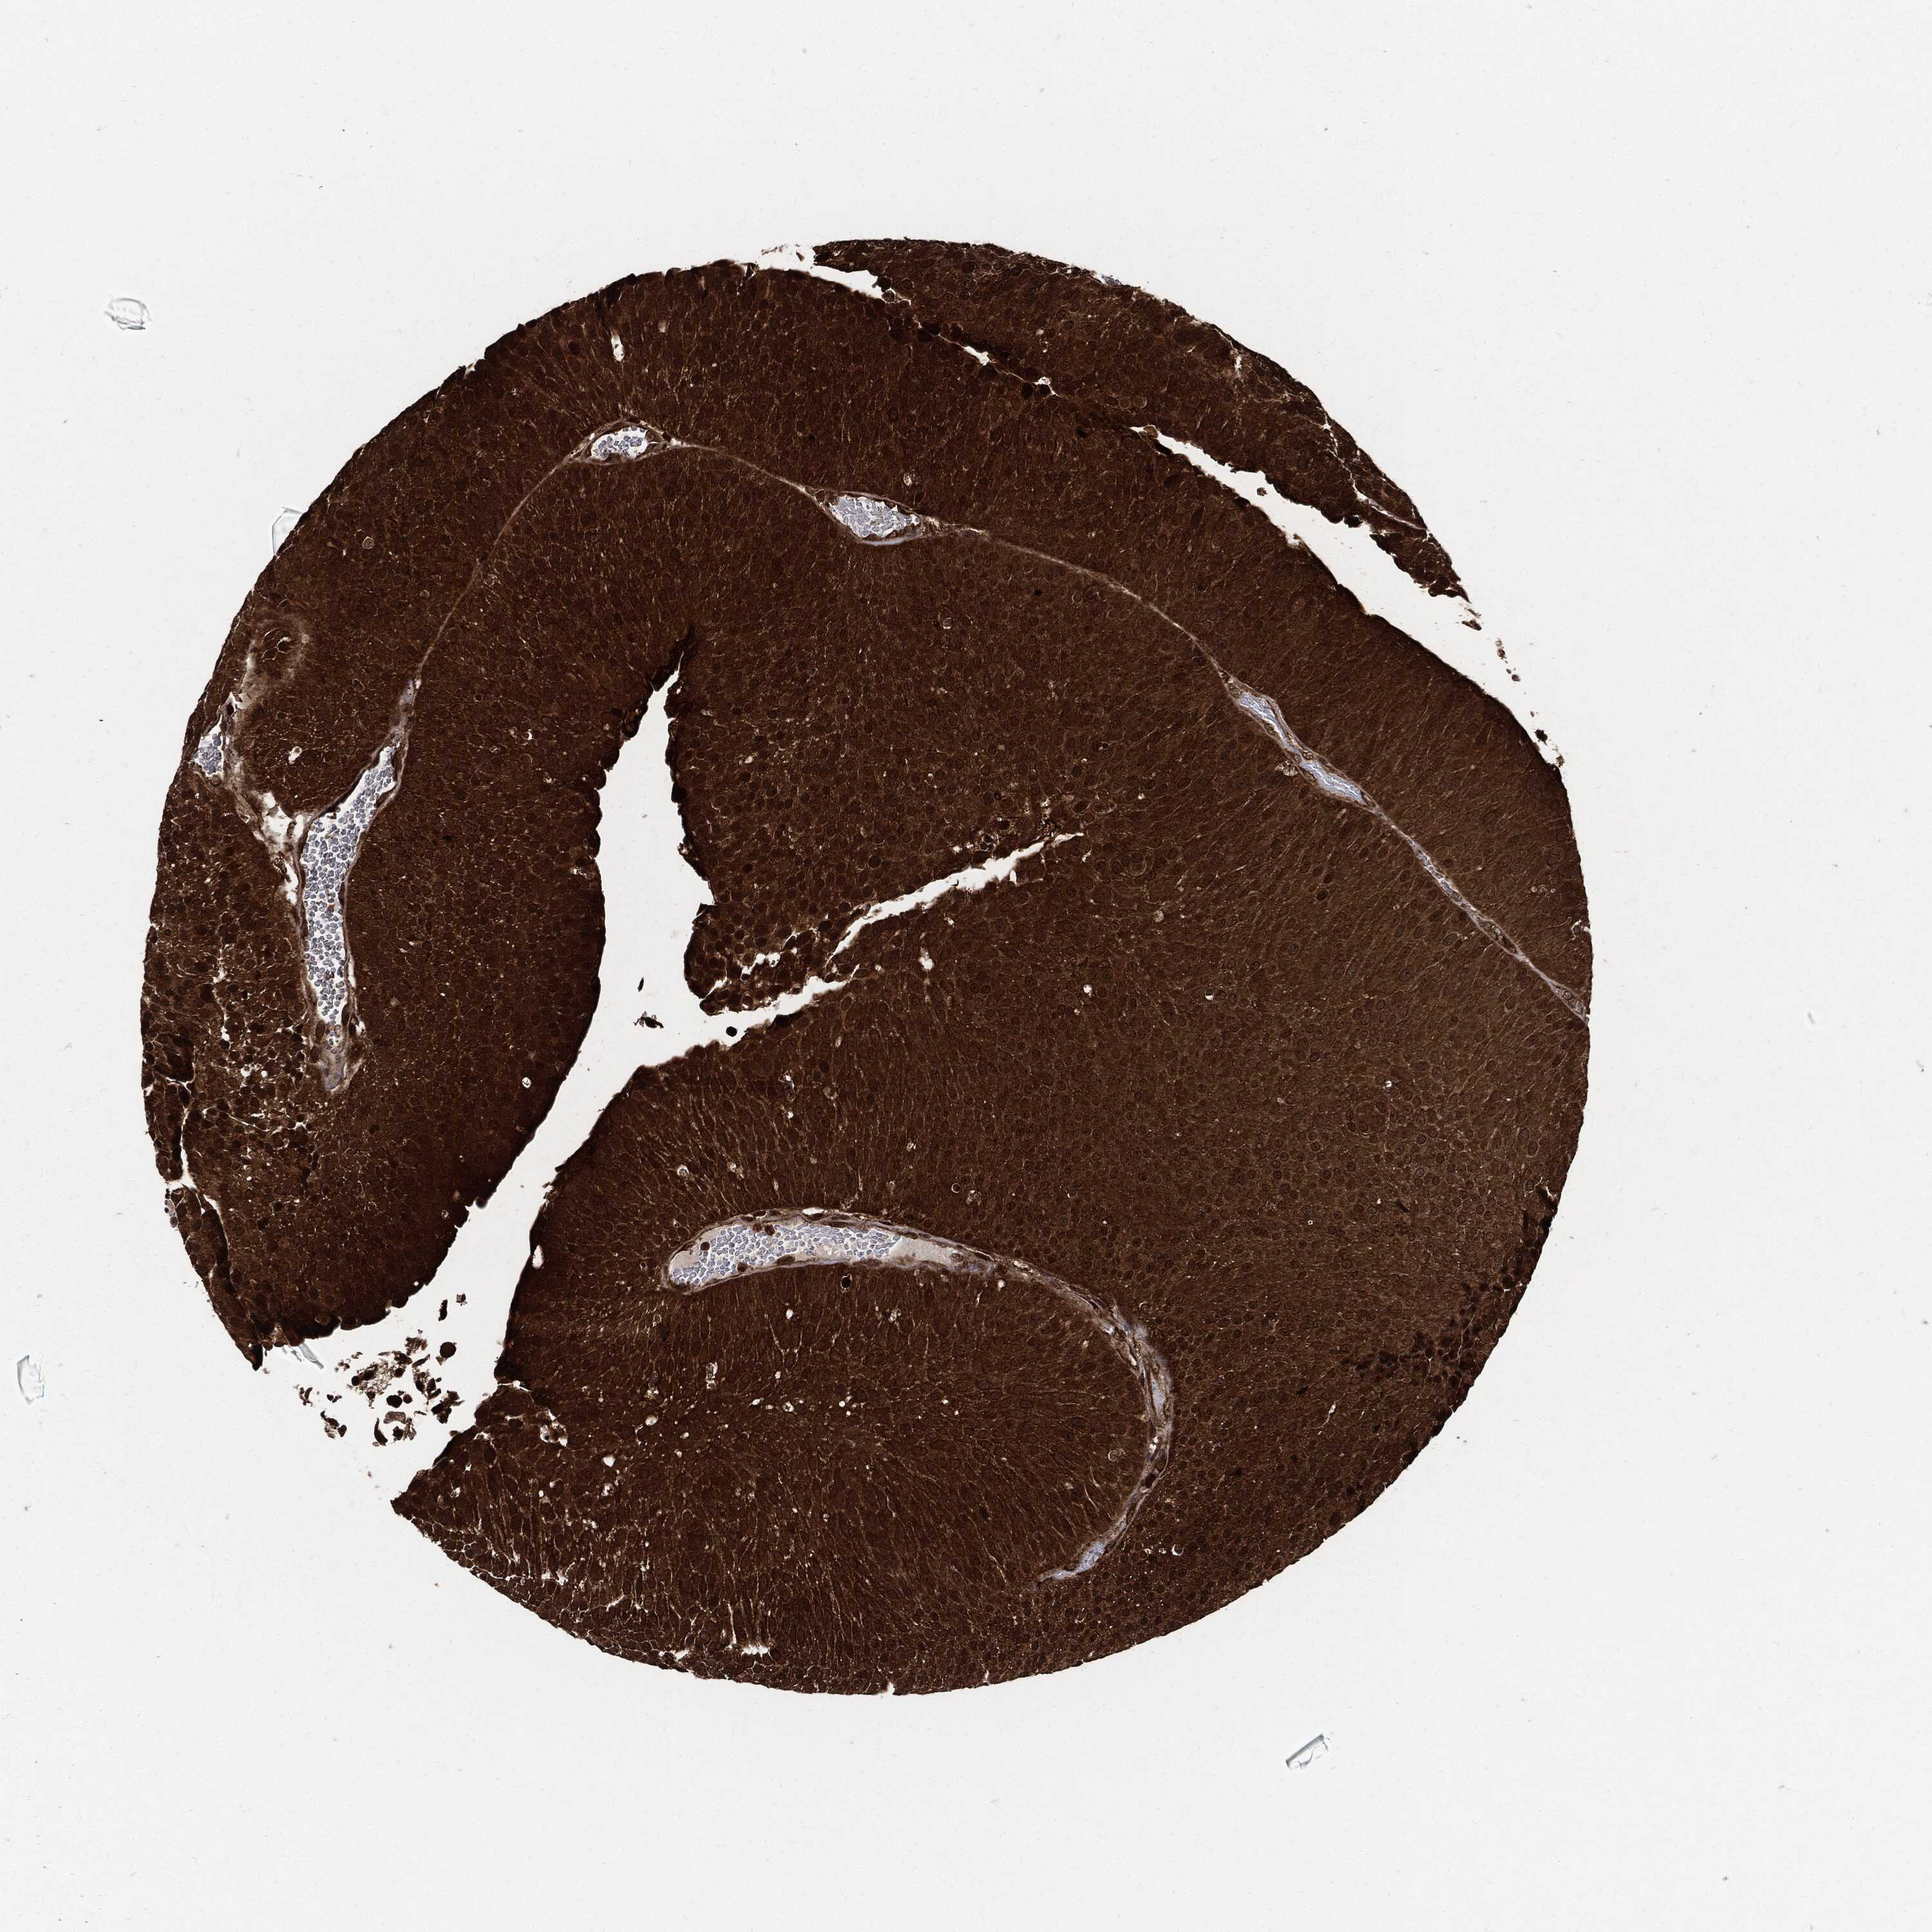

UROTHELIAL CANCER - Protein expressioni

A mouse-over function shows sample information and annotation data. Click on an image to view it in a full screen mode. Samples can be filtered based on level of antibody staining by selecting one or several of the following categories: high, medium, low and not detected. The assay and annotation is described here.

Note that samples used for immunohistochemistry by the Human Protein Atlas do not correspond to samples in the TCGA dataset.

Antibody stainingi

Antibody staining in the annotated cell types in the current human tissue is reported as not detected, low, medium, or high, based on conventional immunohistochemistry profiling in selected tissues. This score is based on the combination of the staining intensity and fraction of stained cells.

Each image is clickable and will lead to virtual microscopy that enables deeper exploration of all samples and also displays staining intensity scores, fraction scores and subcellular localization as well as patient and tissue information for each sample.

Antibody HPA007925

Antibody HPA011212

Antibody CAB003759

Antibody CAB080290

Staining

High

Medium

Low

Not detected

Intensity

Strong

Moderate

Weak

Negative

Quantity

>75%

75%-25%

<25%

None

Location

Nuclear

Cytoplasmic/membranous

Cytoplasmic/membranous,nuclear

Urothelial carcinoma, Low grade

Urothelial carcinoma, High grade